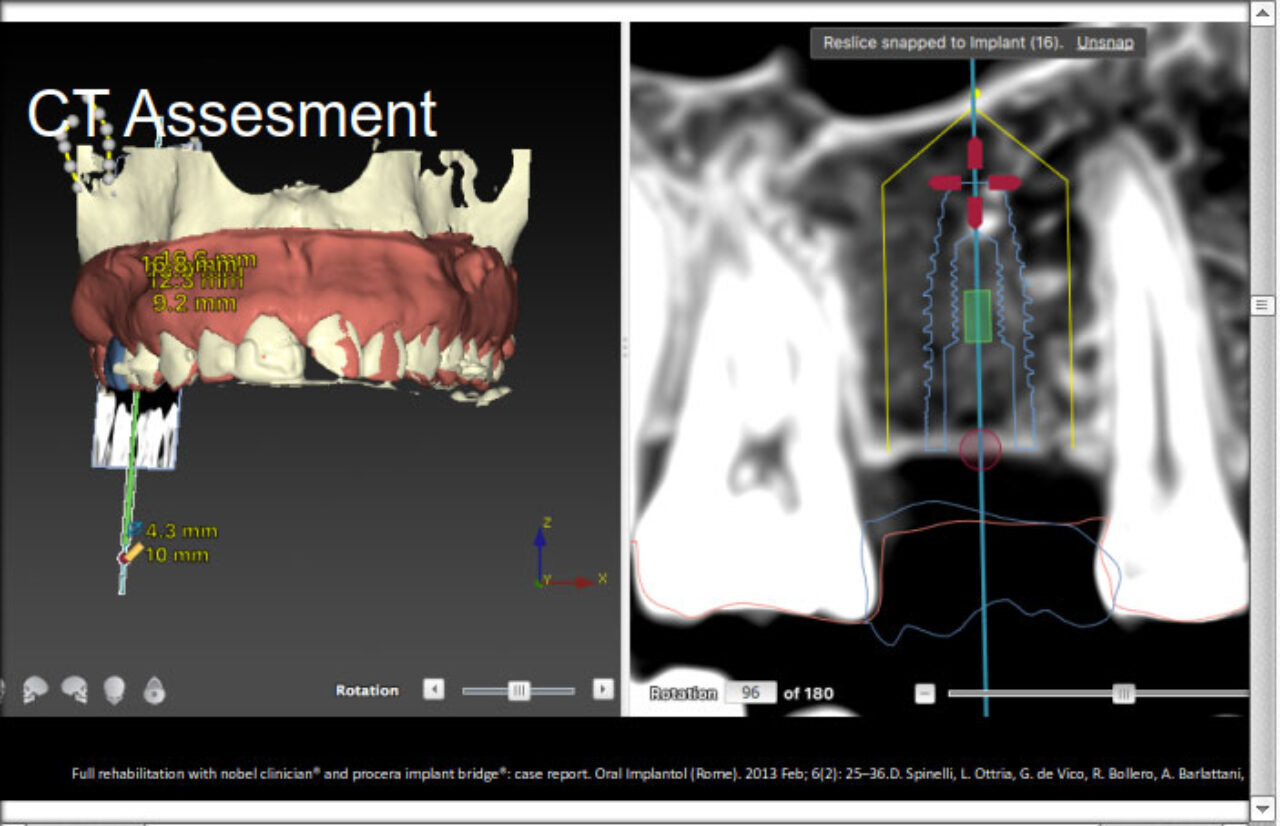

gIDE Library, Cases

Dr. David Azar

Dr. David Azar

Single Implant Placement in the Upper Jaw Non-Esthetic Indication